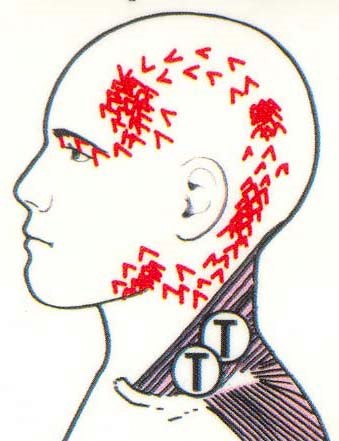

This patient has multiple issues. Her left neck is chronically tight, the left TMJ is painful, and she has regular left temporal headaches. The teeth were retrofitted between the bones in orthodontics and the continued growth of the mandible onl intensified the wedge. The force on this occlusion has been heavy posterior left all her life. The facial profile matches the shape of the force pattern. The history is mostly pain in the TM joints, pain in the teeth at times, but a lifetime history of left side sinus, temporal and neck pain.

The real trick in this case is years of healing . Years down the road the TM joints will clean up and the old muscles patterns down the road are always an issue. It will be a decade of teaching her old anatomy patterns a new trick. An equilibration will need to be done to help achieve some balance and then the patient will be held in a splint at night to protect the TMJs. Regular perio and TMD maintenance is required.